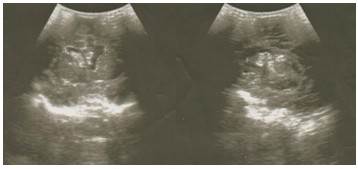

Posteriormente el paciente fue enviado al Servicio de Imagenología donde se le realizó estudio ultrasonográfico transfontanelar con múltiples cortes en los que se observó una imagen ecogénica hacia la región subependimaria e intraventricular derecha. (Figura 1).